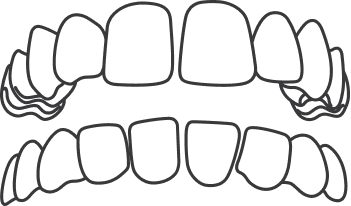

When one or more upper teeth bite on the inside of the lower teeth, this condition is called a crossbite. This can happen on either one or both sides of the jaw and affect front or back teeth.